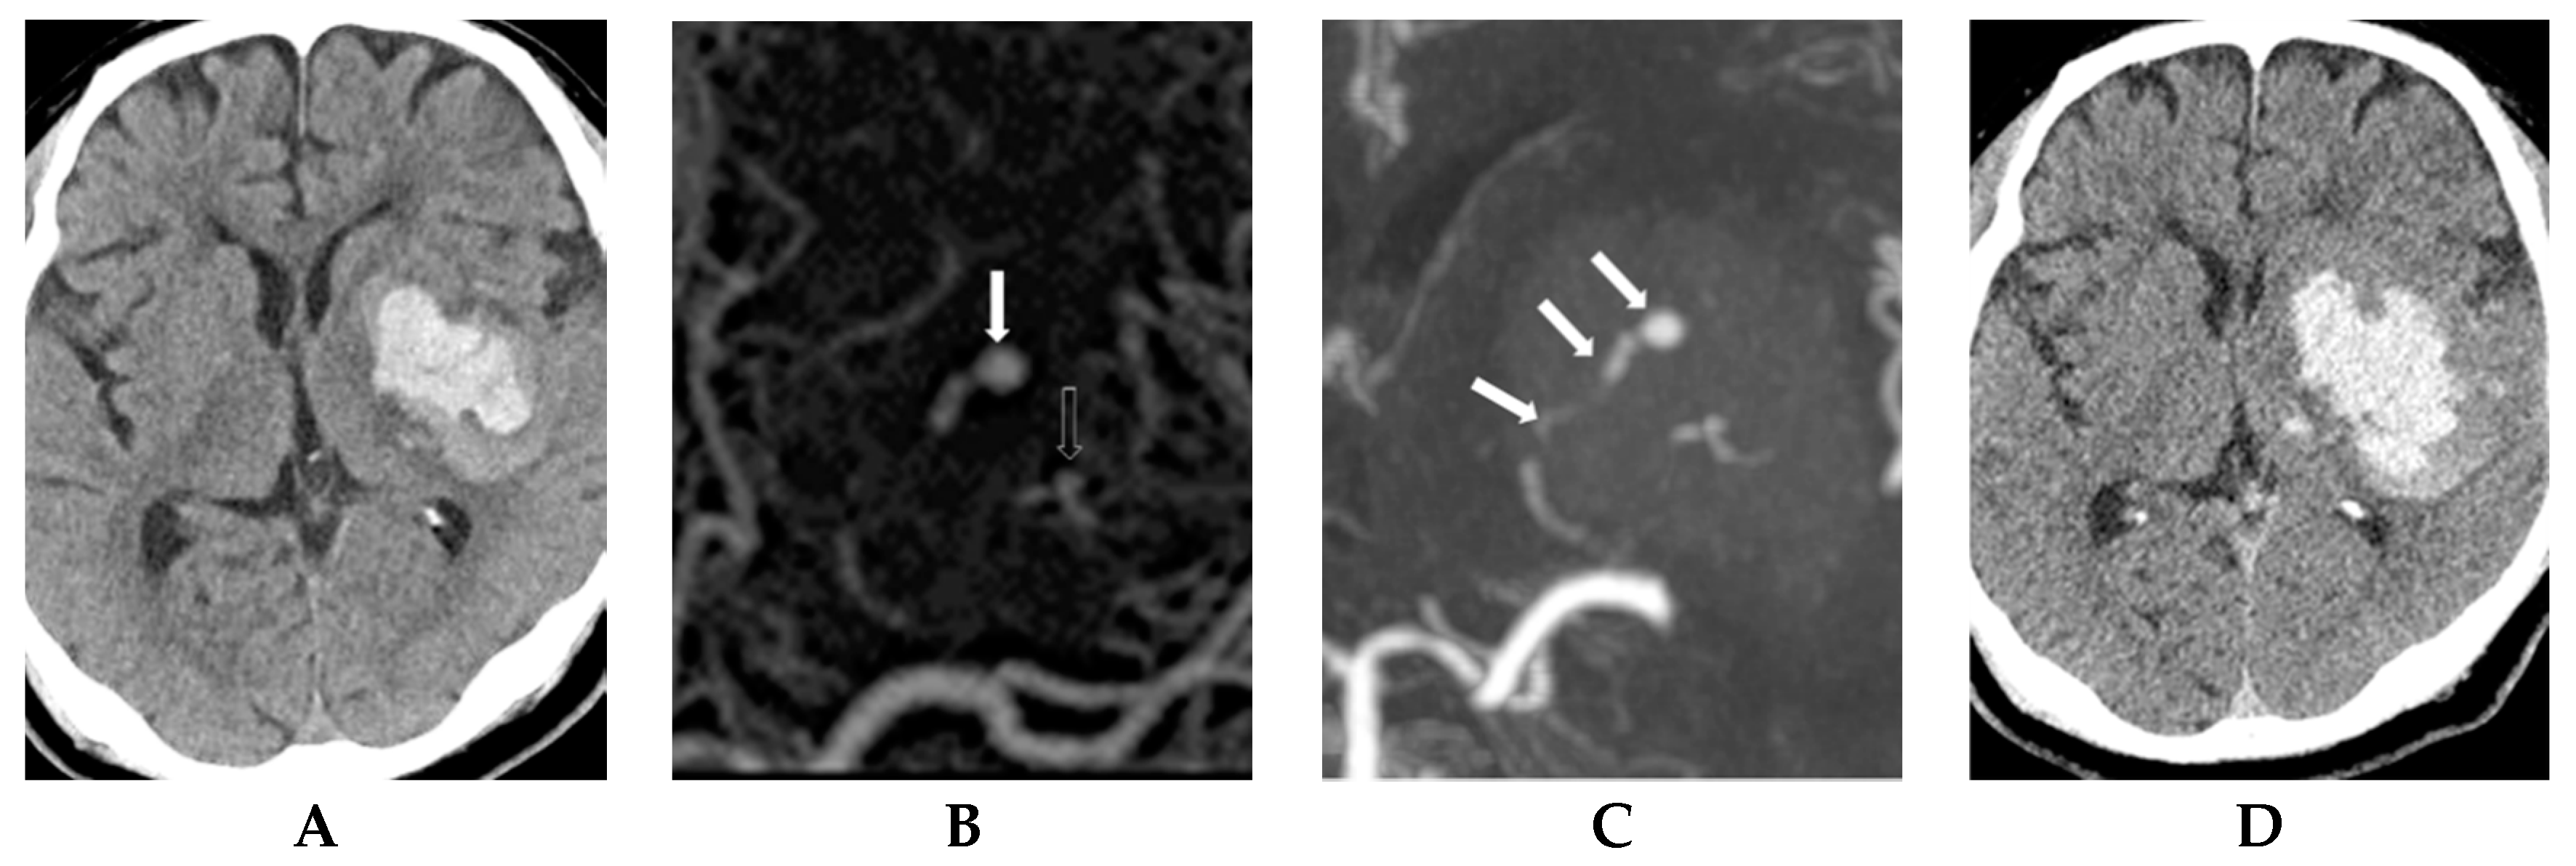

- Park, B.K.; Kwak, H.S.; Chung, G.H.; Hwang, S.B. Diagnostic value of swirl sign on noncontrast computed tomography and spot sign on computed tomographic angiography to predict intracranial hemorrhage expansion. Clin. Neurol. Neurosurg. 2019, 182, 130–135. [Google Scholar] [CrossRef]

- Rodriguez-Luna, D.; Coscojuela, P.; Rodriguez-Villatoro, N.; Juega, J.M.; Boned, S.; Muchada, M.; Pagola, J.; Rubiera, M.; Ribo, M.; Tomasello, A.; et al. Multiphase CT Angiography Improves Prediction of Intracerebral Hemorrhage Expansion. Radiology 2017, 285, 932–940. [Google Scholar] [CrossRef] [PubMed]

- Thompson, A.L.; Kosior, J.C.; Gladstone, D.J.; Hopyan, J.J.; Symons, S.P.; Romero, F.; Dzialowski, I.; Roy, J.; Demchuk, A.M.; Aviv, R.I. Defining the CT angiography “spot sign” in primary intracerebral hemorrhage. Can. J. Neurol. Sci. 2009, 36, 456–461. [Google Scholar] [CrossRef] [PubMed]